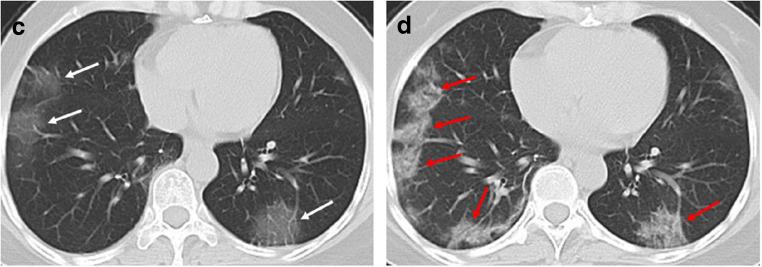

The majority of infected patients had a history of exposure in Wuhan or to infected patients and mostly presented with fever and cough. More than half of the patients presented bilateral, multifocal lung lesions, with peripheral distribution, and 53 (59%) patients had more than two lobes involved. Of all included patients, COVID-19 pneumonia presented with ground glass opacities in 65 (72%), consolidation in 12 (13%), crazy paving pattern in 11 (12%), interlobular thickening in 33 (37%), adjacent pleura thickening in 50 (56%), and linear opacities combined in 55 (61%). Pleural effusion, pericardial effusion, and lymphadenopathy were uncommon findings. In addition, baseline chest CT did not show any abnormalities in 21 patients (23%), but 3 patients presented bilateral ground glass opacities on the second CT after 3-4 days.

SARS-CoV-2 infection can be confirmed based on the patient's history, clinical manifestations, imaging characteristics, and laboratory tests. Chest CT examination plays an important role in the initial diagnosis of the novel coronavirus pneumonia. Multiple patchy ground glass opacities in bilateral multiple lobular with periphery distribution are typical chest CT imaging features of the COVID-19 pneumonia.

大多数感染患者有武汉接触史或感染患者接触史,主要表现为发热和咳嗽。超过一半的患者表现为双侧、多灶性肺部病变,呈外周分布,53 例(59%)患者有两个以上肺叶受累。所有纳入患者中,COVID-19 肺炎 65 例(72%)表现为磨玻璃影,12 例(13%)为实变,11 例(12%)为铺路石征,33 例(37%)为小叶间隔增厚,50 例(56%)为邻近胸膜增厚,55 例(61%)为线状混浊合并。胸腔积液、心包积液和淋巴结病少见。此外,21 例患者(23%)基线胸部 CT 无任何异常,但 3 例患者在第 3-4 天后第二次 CT 检查时出现双侧磨玻璃影。

根据患者的病史、临床表现、影像学特征和实验室检查可以确诊 SARS-CoV-2 感染。胸部 CT 检查在新型冠状病毒肺炎的初步诊断中起重要作用。双侧多发性肺叶多灶性分布的多发性斑片状磨玻璃影是 COVID-19 肺炎的典型胸部 CT 影像学特征。